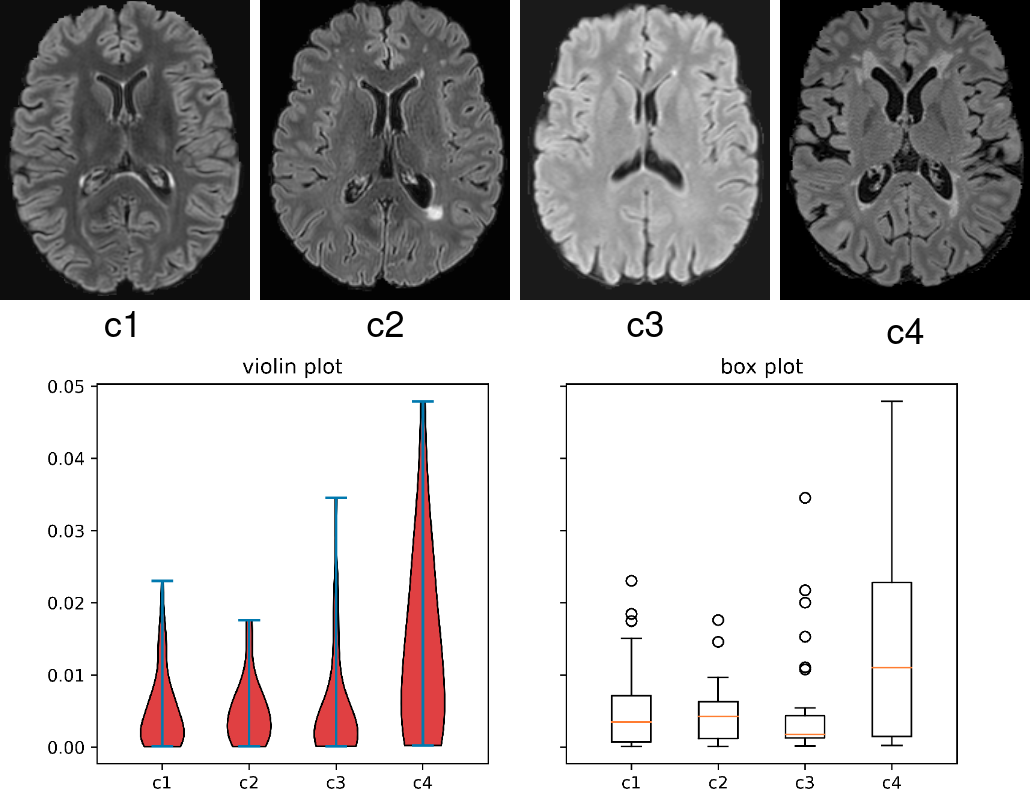

However, current FL methods are suboptimal for multi-client MS lesion segmentation. First, during aggregation, the central server averages the model parameters from all the local clients, assuming each local model has the same importance and performance. For MS lesion segmentation, the datasets from multiple clients, their data distribution and the lesion morphology and signal characteristics can vary greatly [15, 16], which can lead to divergence of the private local models, thereby conferring distinct segmentation characteristics when they are aggregated in the central server. By fusing a model with inferior segmentation performance to others with superior ability, the segmentation performance for the entire updated model may be compromised. Second, differences in the clinical distribution of patients can impact lesion burden, size and morphology at a client level, generating significant inter-site variance in multi-client studies, as shown in Fig. 1. As explored in [17, 18], a model trained on a dataset with smaller lesions will usually present a lower performance due to the lack of lesion samples for training. However, the task loss functions in each client are optimized with the same importance in previous FL methods [9, 11, 10], which would induce the inferior performance of the center model on the clients with smaller lesion sizes, and further influence the overall FL segmentation accuracy.

Another challenge in FL MS lesion segmentation tasks is the heterogeneity of lesion size across different clients. As indicated in [17, 18], lesions with smaller sizes should be assigned a larger weight during model training. To this end, we further propose to re-weight the segmentation loss functions in each client defined in Equation 1 based on the lesion volume.

For the round of local training in client , we first calculate the average lesion volume ratio of all the data samples for training. Specifically, the lesion ratio in each training patch is the ratio of the lesion volume to the brain volume. Compared with only counting the voxel number of lesions, the lesion volume ratio can avoid inaccurate estimations when the proportions of the brain volume in some specific training patches are small. Next, the is accumulated with the average lesion volume ratio from the previous round, denoted as . With the increase of , the accumulated can represent the true lesion volume ratio for the data used during the model training process in each client. In the round of local training, the segmentation loss in Equation 1 is then reformulated as: